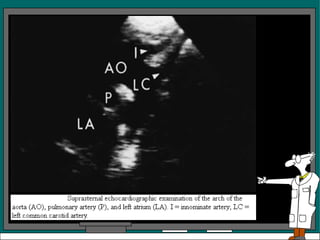

Vista Supraesternal

• Es una vista paralela o perpendicular al arco

de la aorta

• En la vista paralela se ve la aorta, la arteria

pulmonar y la auricula izquierda, con la

tecnica de barrido se podria visualizar

tambien la arteria innominada, la carotida

izquierda y la subclavia izquierda

• Un examen supraesternal en el eje corto del

arco de la aorta, revela una aorta circular, la

arteria pulmonar y parte de la auricula

izquierda, se observa tambien la bifurcacion

de la arteria pulmonar.